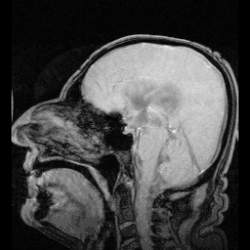

Ликвор циркулирует в субарахноидальном пространстве вокруг головного и спинного мозгов, а также в желудочках головного мозга

Циркуляция

Ликвор образуется в мозге: в эпендимальных клетках сосудистого сплетения (50—70 %), вокруг кровеносных сосудов и вдоль желудочковой стенки. Далее цереброспинальная жидкость циркулирует от боковых желудочков в отверстие Монро (межжелудочковое отверстие), затем — вдоль третьего желудочка, проходит через Сильвиев водопровод. Затем проходит в четвёртый желудочек, через отверстия Мажанди и Лушки выходит в субарахноидальное пространство головного и спинного мозга. Ликвор реабсорбируется в кровь венозных синусов и через грануляции паутинной оболочки.